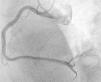

A 56-year-old Caucasian man with no known history of disease and not taking regular medication was admitted to our hospital with retrosternal chest pain of two hours’ duration. Physical examination showed him to be hemodynamically stable, with no abnormalities on cardiac or pulmonary auscultation. ST-segment elevation was seen in leads II, III and aVF on the 12-lead ECG. Urgent coronary angiography by a right radial approach showed a dominant right coronary artery occluded by thrombi throughout its length; no lesions were observed in the other coronary arteries (Figure 1). Primary angioplasty of the occluded right coronary was performed and the thrombi were aspirated using a 6F Export© AP© aspiration catheter (Medtronic Vascular, Santa Rosa, California, USA) and placed in the receptacle. Since the thrombi had become trapped when the aspiration catheter was inserted, the catheter had to be completely withdrawn in order to extract them. Several thrombi, the largest over 30 mm in length, were removed (Figure 2).

Balloon angioplasty was successful, with no residual lesion and with final TIMI flow 3 (Figure 3).